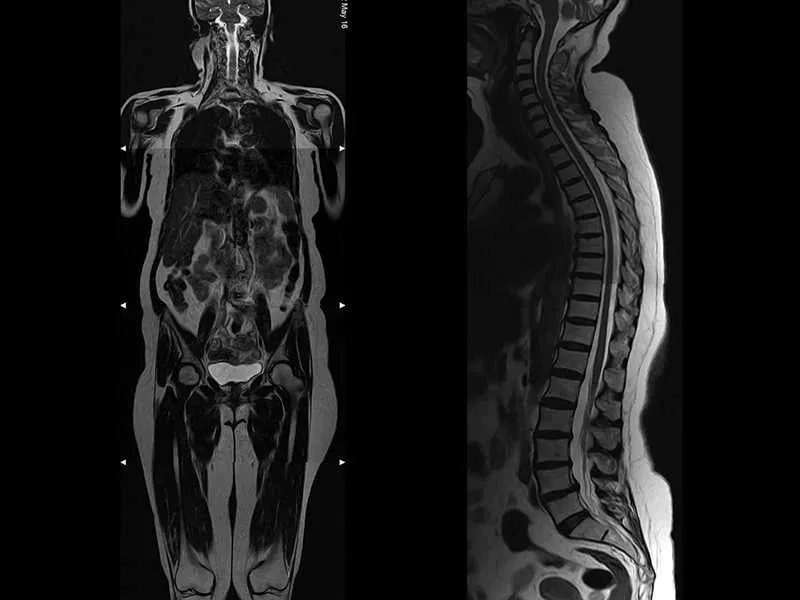

Tüm vücut MR, manyetik rezonans görüntüleme teknolojisi kullanılarak vücudun tamamının ayrıntılı bir şekilde taranmasıdır. Radyasyon içermeyen bu yöntem, manyetik alan ve radyo dalgaları yardımıyla organların ve dokuların yapısını detaylı bir şekilde gösterir. Doktorlar, bu görüntüleri kullanarak hastalıkları teşhis eder ve tedavi planlarını oluşturur.

Tüm Vücut Emar için kullanılan MR Cihazlarımız en yeni teknolojiye sahip 3 Tesla özelliğine sahiptir. Tüm Vücut Emar yüksek çözünürlüklü ve çok net görüntüler doğru teşhis için son derece önemlidir. Tüm Vücut emar için anestezili seçenekler de mevcuttur.

Tüm vücut MR, özel bir cihazda yatay pozisyonda yatarak gerçekleştirilir. Hasta, cihazın içinde hareketsiz kalır ve manyetik alan ile radyo dalgaları yardımıyla görüntüler elde edilir.